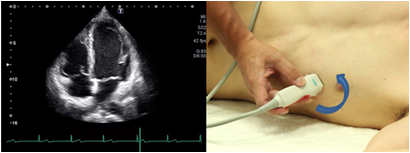

Apical 2 chamber view

The apical 2 chamber view can be obtained by the 90 degrees counterclockwise rotation of the probe from the position of visualizing the apical 4 chamber view. The proper view does not include the right chamber or the anterior papillary muscle. This view is suitable for evaluation of wall motion abnormalities in the anterior and inferior walls of the left ventricle and measurement of left ventricular volume and left ventricular ejection rate.